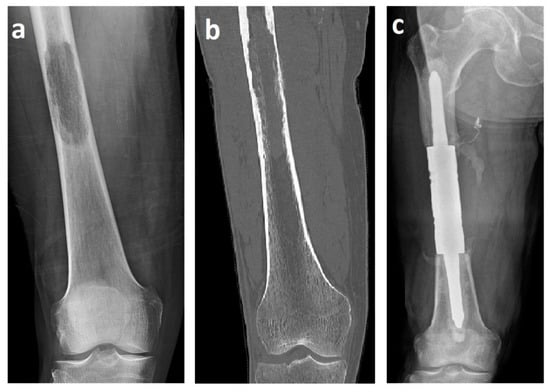

The mean length of the resection and bone defect was 11.2 cm (range 8–16 cm). An intercalary endoprosthesis with cemented stems was used in all cases. The implant consists of a central spacer clamped onto a proximal and distal intramedullary stem. Canals were reamed proximally and distally with flexible reamers. Endoprosthetic body segments were placed, and proper rotation was determined by pre-resection marks placed in the proximal and distal aspects of the affected bone. The intramedullary stems were fixed at the proximal and distal bone stumps with polymethylmethacrylate (PMMA). Then, the spacer was assembled in situ with the stems using interconnection screws (Figure 1).

Figure 1.

X-ray (a) and computed tomography (b) images of renal cell carcinoma solitary metastasis to the femoral diaphysis. X-ray image (c) after resection with a cemented intercalary endoprosthesis. These images are from patient 2 in Table 1.